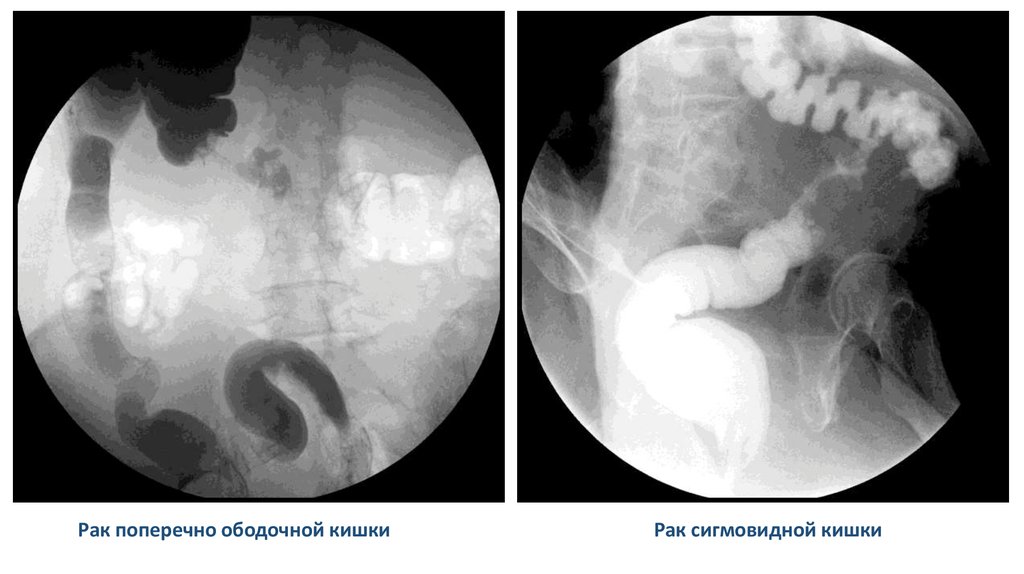

Рак поперечно ободочной кишки

Рак сигмовидной кишки